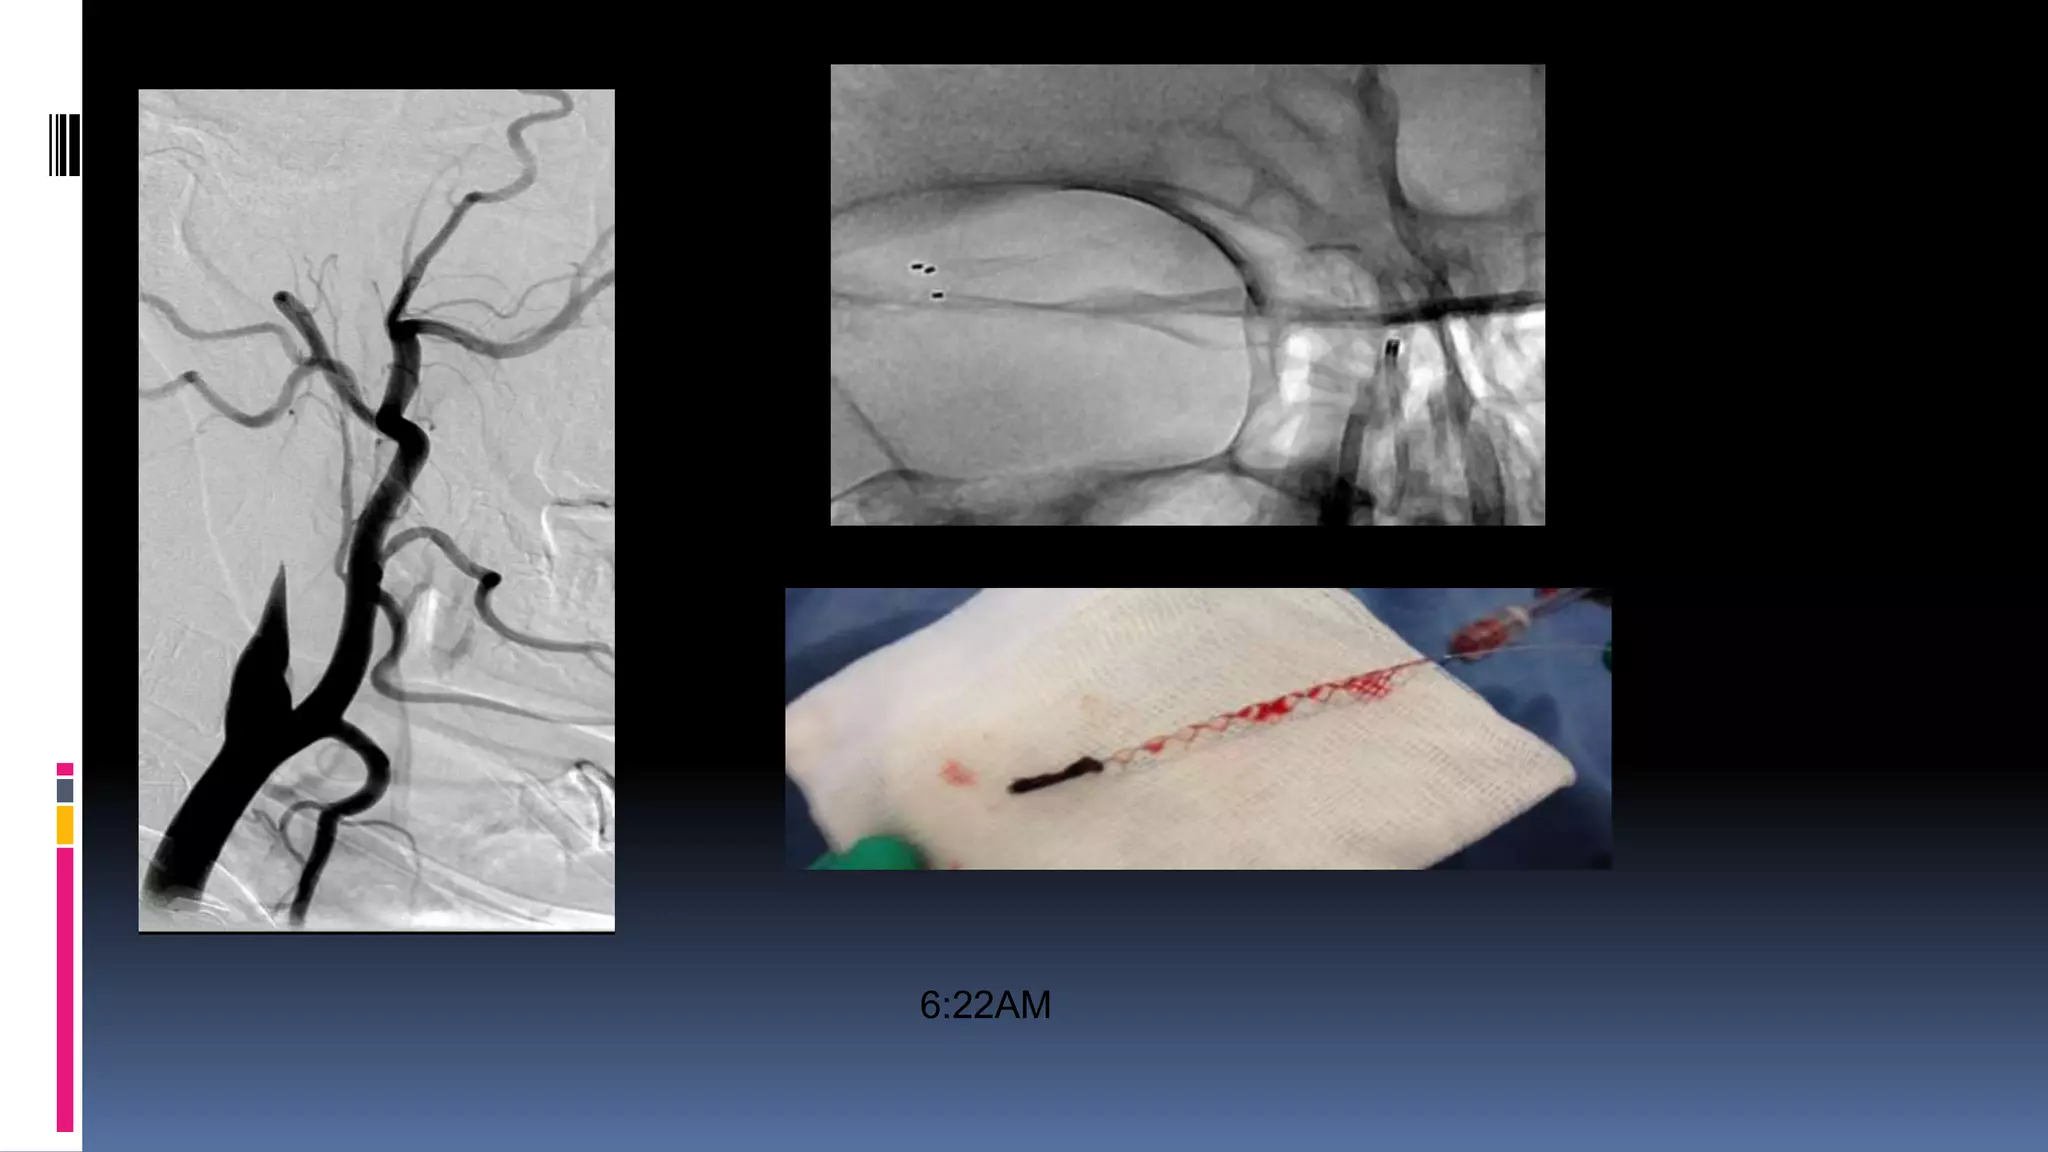

 Left hemiplegia, left UL and LL 0/5

 5:14AM

6:22AM

8:07 AM

Patient made gradual recovery

Left LL 4/5 and UL 3/5 - 30 day follow up mRS at 90

days- 0

Patient presented with in 2 hours

Futile IV tpa